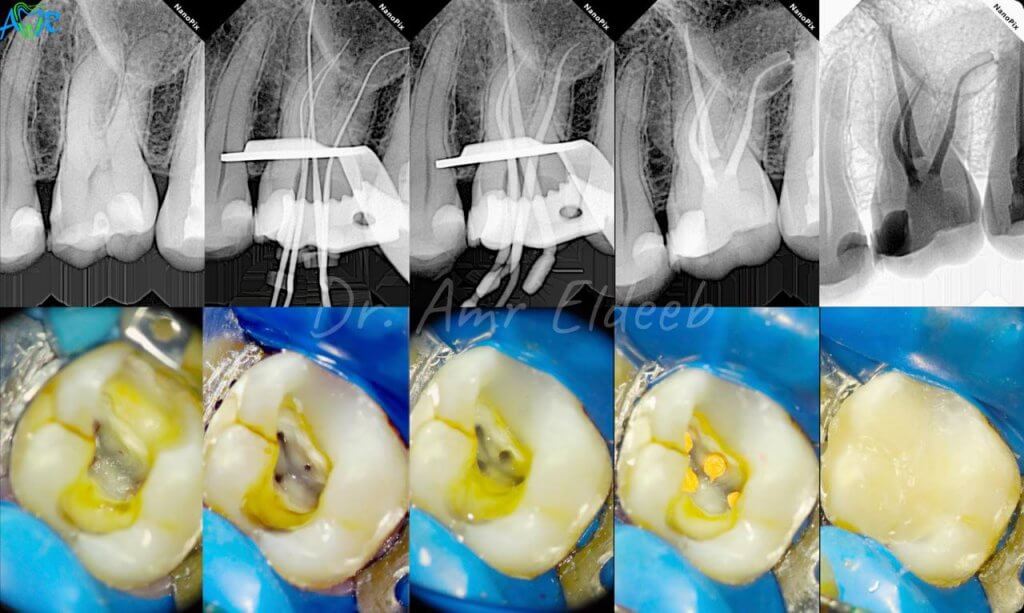

علاج جذور الأسنان

ما هو علاج جذور الأسنان (Root Canal)؟

علاج جذور الأسنان هو إجراء يهدف إلى:

- إزالة الجزء المصاب أو التالف داخل السن.

- تنظيف داخل السن.

- إغلاقه (حشوه) للحفاظ على صحته.

- ترميم السن بحشوة ثم وضع تاج (كراون).